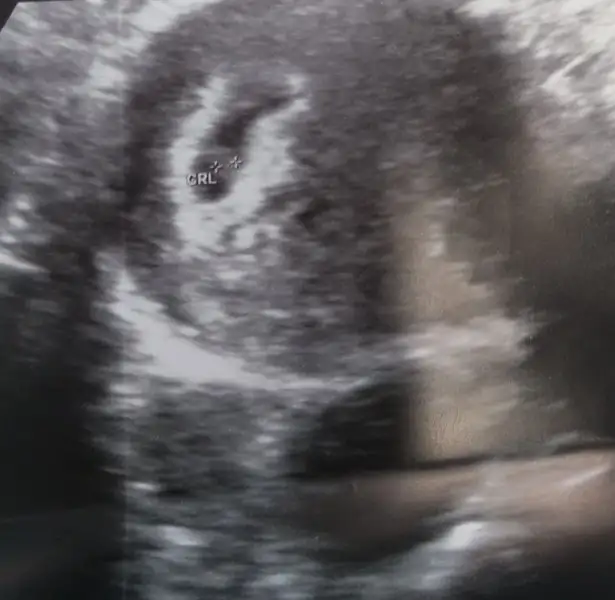

Bu da benim minis .. bakalım bende öğrenince yazarım..

Ay inşallah ya.. Bir kızım var zatencanım senin erkek gibi yaaaaaa valla umutlandırmakta istemiyom ama ne bilim içimden hep öle geçiyo teoriler vs de onu gösteriyo zaten.